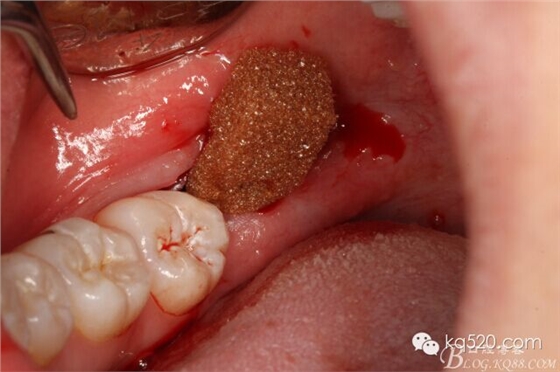

圖8.小牙挺挺松48.

圖9.拔除48.

圖9.放膠質銀、無需縫合。

手術特點: 小切口、術后 反應輕、無腫脹、不縫合、手術時間短。